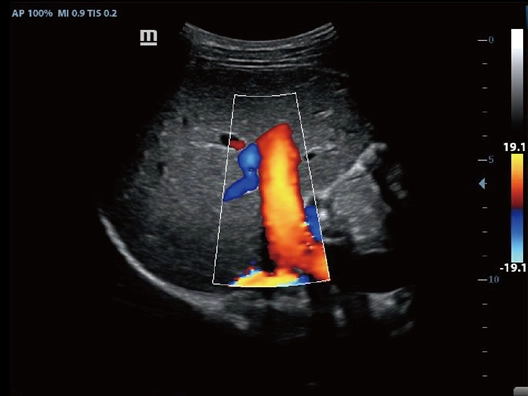

Клинические изображения

- Режимы сканирования: B/M/Color Dopler/Color M/Power/Directional Power Doppler Flow Imaging

- NTE (компрессионная эластография), поддержка исследований с контрастом и широкий выбор опций для акушерства/гинекологии, в том числе в режиме 3D/4D.